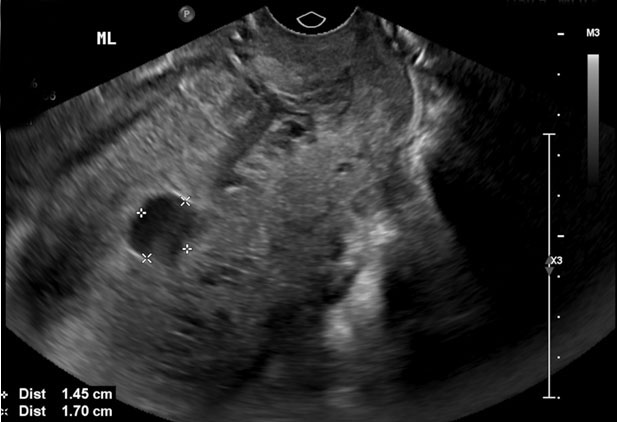

On hospital day 1, a repeat hemoglobin showed a slight drop from 8.9 g/dL on admission to 7.7 g/dL. She remained hemodynamically stable and only minimal vaginal bleeding was noted on physical exam. Findings from her formal pelvic ultrasound were concerning for a pseudoaneurysm as there was a hypoechoic area within the midportion of her uterus, extending into the endometrium and measuring 1.5×1.2×1.7 cm. Color flow Doppler showed a swirling of blood within this hypoechoic area and a connecting vessel in the left posterior aspect of the uterus (Figure 1 and Figure 2). Following interventional radiology consultation, decision was made to conservatively manage the uterine bleeding with uterine artery embolization to preserve fertility in this patient. Post-procedure findings were notable for a large pseudoaneurysm visualized from the right uterine artery. Gelfoam and 2 micro coils were utilized to achieve hemostasis in the right uterine artery.

Figure 2: A hypoechoic area within the midportion of the uterus, extending into the endometrium measuring 1.5×1.2×1.7 cm.